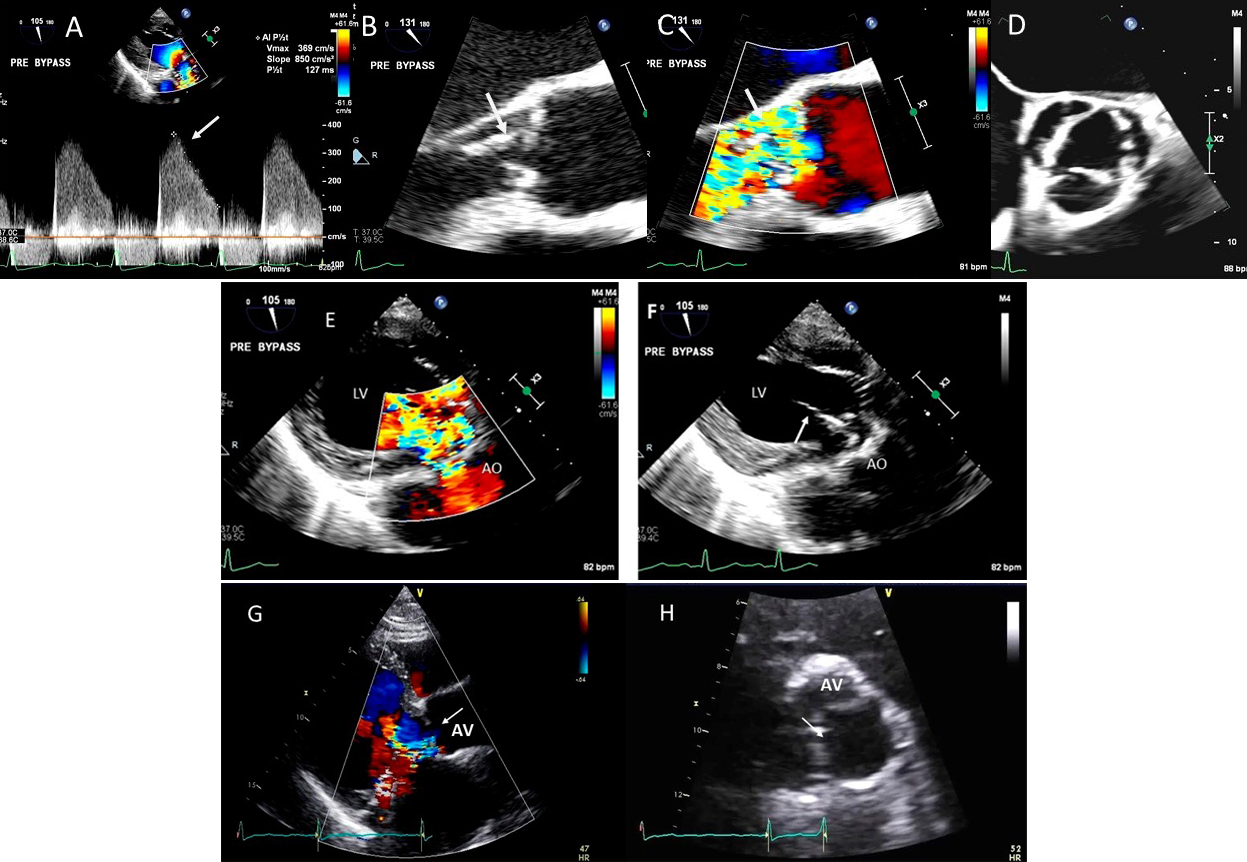

Fig. 10.Endocarditis induced aortic cusp tear and aortic regurgitation (AR) demonstrated by TEE: (A) TEE transgastric (TG) view showing dense CW Doppler signal of AR with a steep slope, (B) Mid esophagel (ME) long axis view showing torn and flail aortic valve cusp, (C), same view showing severe AR on color Doppler, (D) ME short axis view showing a tricuspid aortic valve, (E) TEE TG view showing dilated LV and severe AR on color Doppler and (F) torn AV leaflet on 2D. (G) transthoracic parasternal long axis view showing a dilated LV and poorly defined AR on color Doppler, (H) transthoracic AV short axis view with an ill-defined view showing possible of the torn left coronary cusp (white arrow).